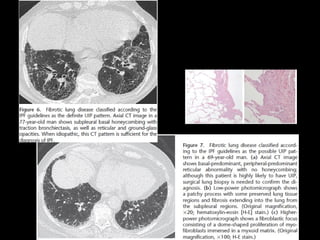

Fibrosis pulmonar idiopática •Causa desconocida • Es la más común de IIP 50-60% • Patrón histológico y TC: UIP exposición a drogas y polvo, neumonitis hipersensibilidad crónicas, colágeno y asbestosis D: excluir causas

FPI • >50 ,h • Síntomas gradual, disnea, tos seca • No responde a corticoides • Pronóstico pobre, 2-4 SV • Muerte: falla respiratoria, cor pulmonare • Secundario: mejor pronóstico

UIP histología • Combinaciónheterogénea de inflamación intersticial, fibrosis y panalización con áreas normales • *biopsia puede desestimarse

UIP TC • Fibrosiscon áreas normales. • Disminución de volumen pulmonar • Opacidades reticulares • Vidrio esmerilado • Predominio en regiones basales y subpleurales • Distorsión arquitectónica con bronquiectasias por tracción secundaria a fibrosis. • Panal de abejas (2-20mm) • Linfoadenopatías mediastínicas pequeñas.

DD UIP CT •AR, Esclerodermia (esófago dilatado) • Asbestosis ( derrame pleural, bandas parenquimatosas) • Neumonitis por hipersensibilidad crónica: fijarse en signos de atrapamiento aéreo, Respeto de bases o cuando hay nódulos centrolobulillares. • Sarcoidosis terminal: fibrosis en segmentos posteriores de lóbulos superiores o perihiliar, o nódulos perilinfáticos. • NSIP • Complicaciones: • Exacerbación, DAD • Cáncer pulmonar 10-15% bases